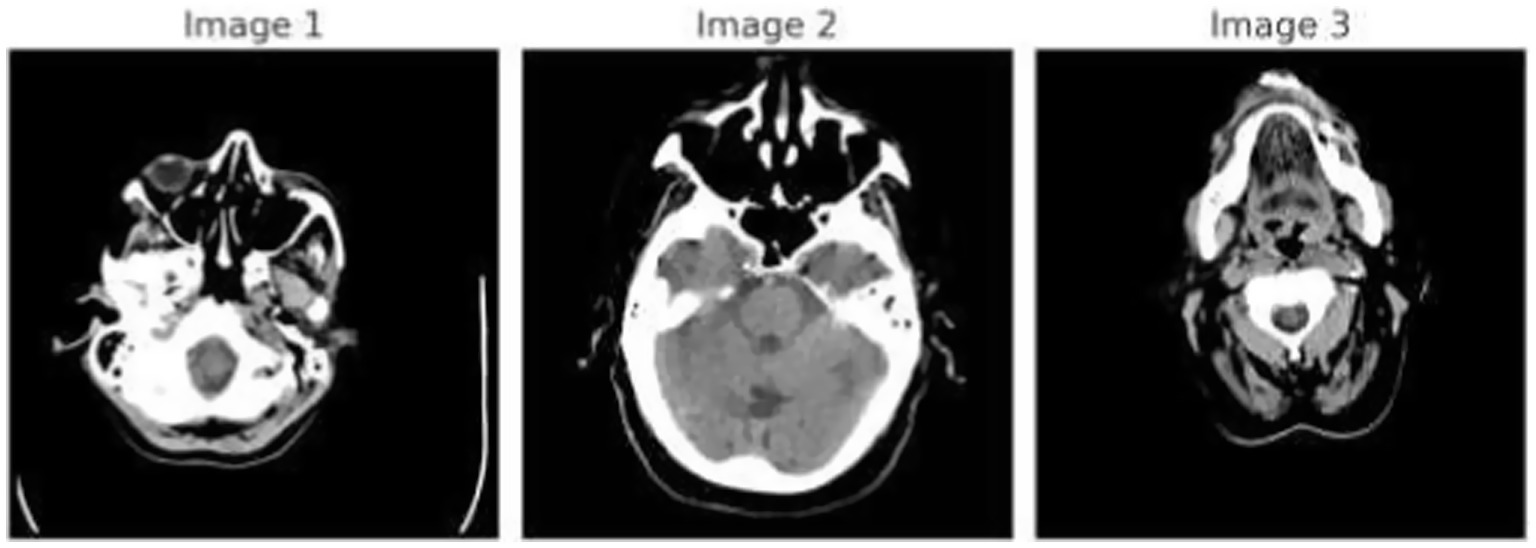

Figure 1 demonstrates the unprocessed and processed CT scan brain scans. Raw images are initially scanned, whereas the processed ones have undergone a procedure of removing noise and normalization to facilitate analysis. Figure 2 shows grayscale, equalized, and edge-detected images of the preprocessed brain images. Gray levels eliminate color, equalization increases contrast, and edge detection emphasizes boundaries of key structures. The CT scan cross-sections shown in Figure 3 are used to obtain details about brain structure and the parts prone to abnormalities such as strokes and tumors. Figure 4 shows different CT scan cross-sections with varying types of stroke, and how ischemic and hemorrhagic strokes can be represented in the brain in a cross-section.

CT scan cross-sections showing brain structure and potential abnormalities.

Figure 4

CT scan cross-sections of brain showing stroke variants.